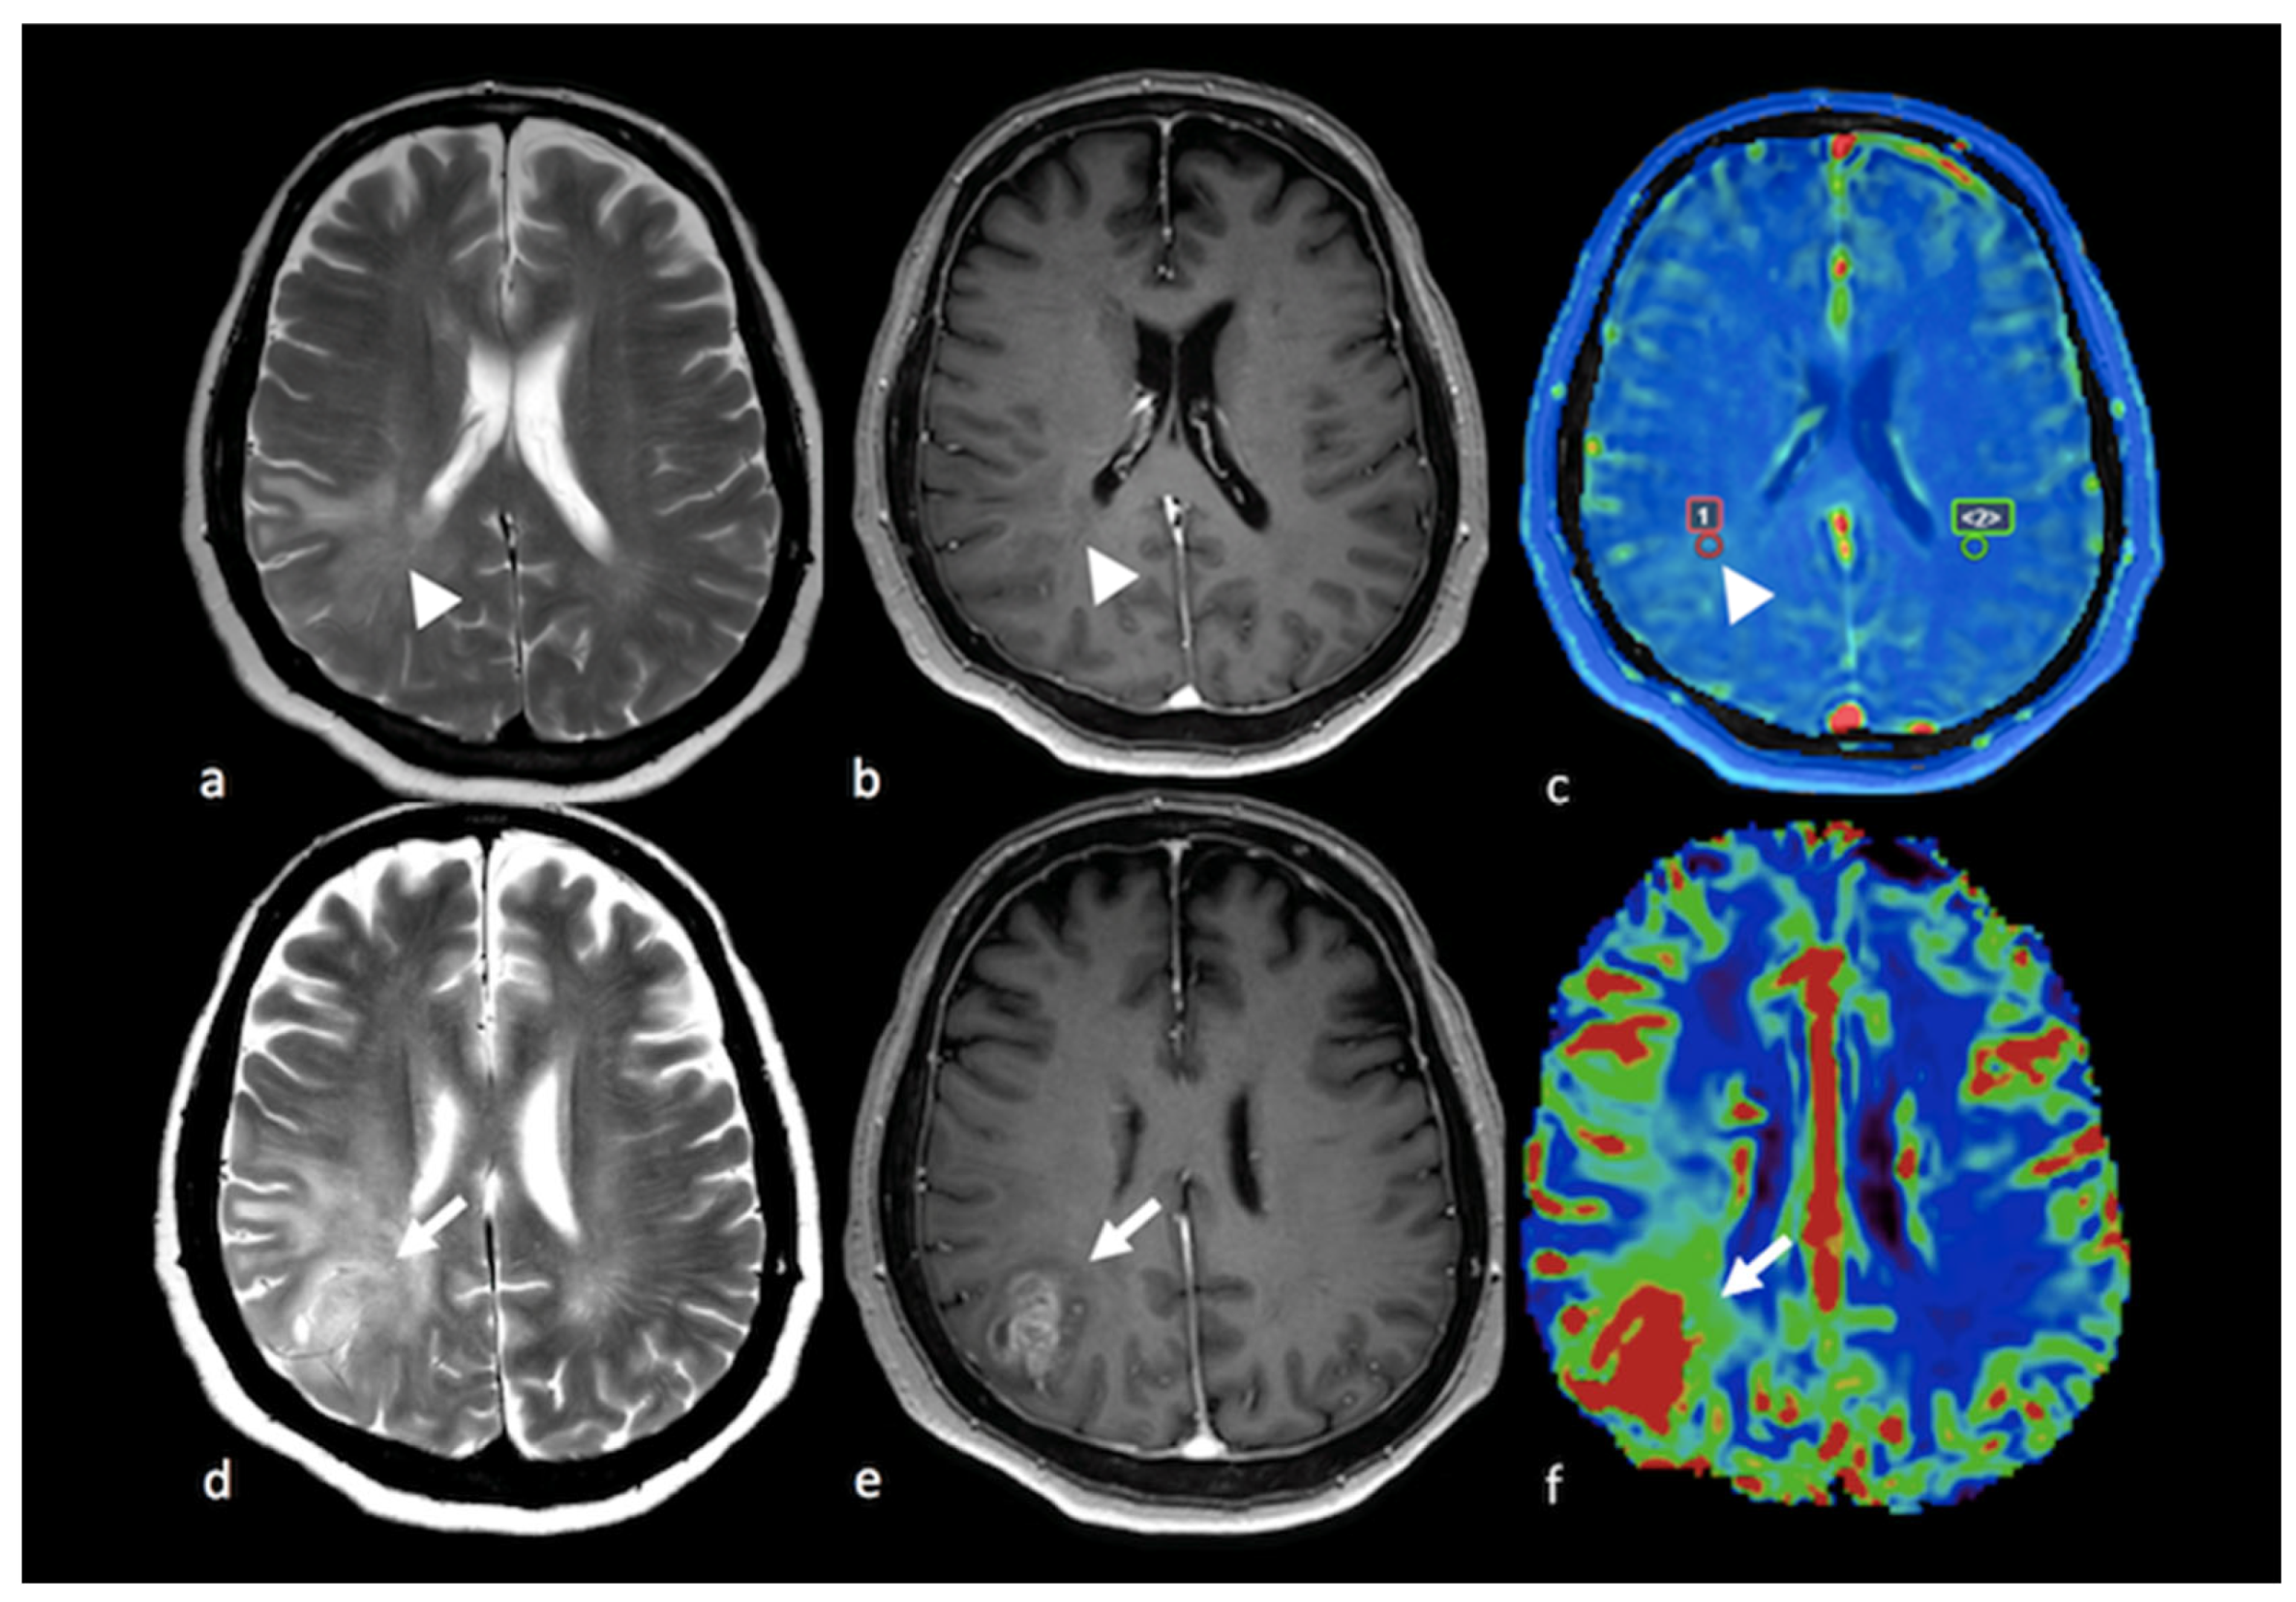

3.2.2. Diffusion Tensor Imaging (DTI)

- Lee, E.J.; Ahn, K.J.; Lee, E.K.; Lee, Y.S.; Kim, D.B. Potential role of advanced MRI techniques for the peritumoural region in differentiating glioblastoma multiforme and solitary metastatic lesions. Clin. Radiol. 2013, 68, e689–e697. [Google Scholar] [CrossRef]

- Byrnes, T.J.; Barrick, T.R.; Bell, B.A.; Clark, C.A. Diffusion tensor imaging discriminates between glioblastoma and cerebral metastases in vivo. NMR Biomed. 2011, 24, 54–60. [Google Scholar] [CrossRef] [PubMed]

- Sternberg, E.J.; Lipton, M.L.; Burns, J. Utility of diffusion tensor imaging in evaluation of the peritumoral region in patients with primary and metastatic brain tumors. AJNR Am. J. Neuroradiol. 2014, 35, 439–444. [Google Scholar] [CrossRef]